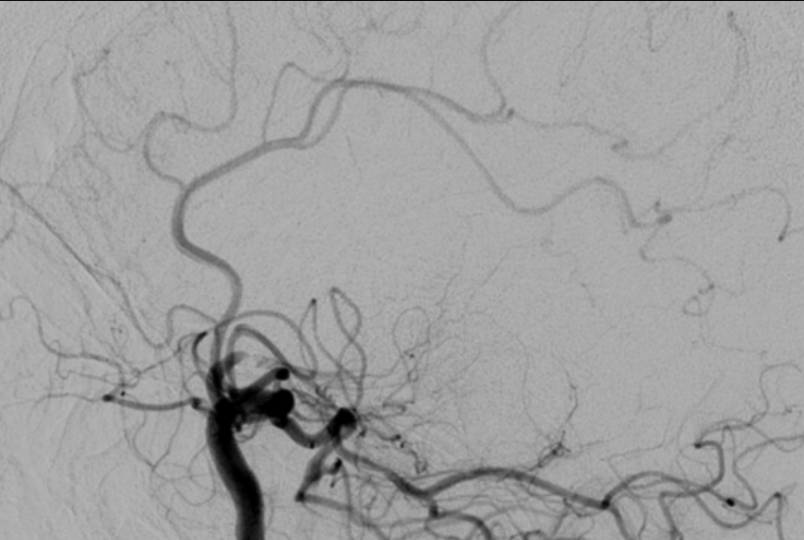

Brain Arteriovenous Malformation (AVM)

An arteriovenous malformation (AVM) is a vascular malformation of the brain and spinal cord. Within the vascular system there is a fast (high pressure) delivery of nutrients and oxygen in the arteries and a slow (low pressure) return of waste back to the heart and lungs. Capillaries, nutrient exchange centers throughout your body, are what safely bridge the high pressure arteries to the low pressure veins. In patients with AVM these capillaries are entirely absent and instead there is a dangerous, abnormal connection between the high pressure arteries and the low pressure thinly-walled veins, which are not biologically designed to handle high arterial pressures.